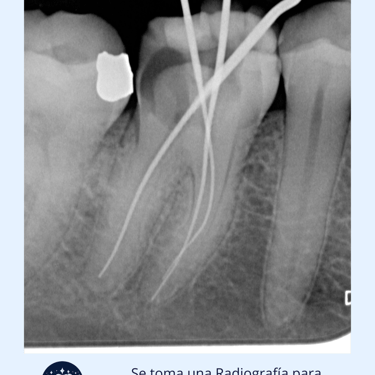

Evaluación Inicial: Examen clínico y radiografías para determinar la extensión del daño o infección.

Limpieza y Desinfección: Se eliminan la pulpa y los tejidos infectados del conducto radicular utilizando limas endodónticas. El conducto se limpia y desinfecta con soluciones antimicrobianas.

Instrumentos: Explorador dental, radiografías, limas endodónticas, gutapercha, selladores.